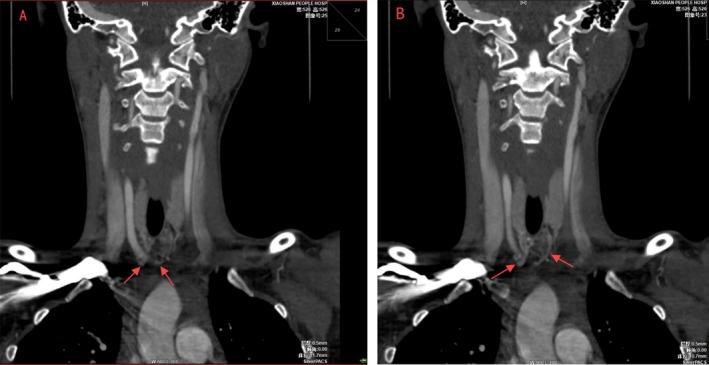

Intraoperative findings unexpectedly identified two small arteries originating from the brachiocephalic trunk. These were later confirmed as bilateral TIAs through postoperative imaging and 3D reconstruction.

The patient recovered uneventfully, with no complications. Postoperative imaging validated the intraoperative findings, confirming the unique vascular variation.

术中意外发现两条起源于头臂干的小动脉。术后影像学检查和三维重建后来证实这些为双侧甲状腺最下动脉。

患者恢复顺利,无并发症。术后影像学检查证实了术中发现,确认了这种独特的血管变异。